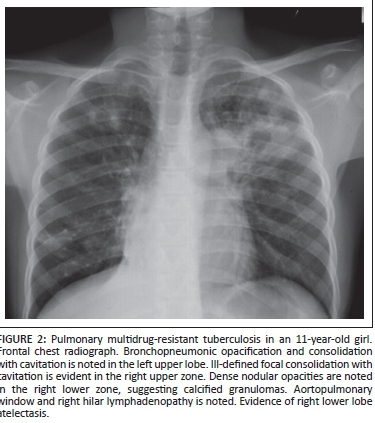

- Cavity formation: liquefaction of caseous material. Fibrous tissue usually around periphery of lesions

What does a CXR of TB look like?